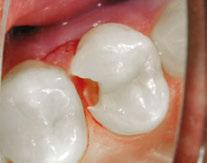

Case 2

A 3-year-old female presented with pulpal necrosis and abscess on #E and pulpal necrosis on #F. Extraction therapy or pulpectomy was offered. The family was highly motivated to retain #E and #F. The pulpectomy was performed with 0.02 K-Flex hand files, 3% NaOCl with a lateral vented needle, obturated with Vitapex (Neo Dental International Inc., Federal Way, Washington), a premixed paste of calcium hydroxide and iodoform. The access was filled with a HVGIC sealing the pulp therapy and increasing the clinical success by minimizing the potential for bacterial contamination. NuSmile ZR anterior crowns were selected as offering a full-coverage, esthetic, cemented restoration with no polymerization shrinkage when compared to a composite restoration. Crowns were cemented with NuSmile® BioCem (NuSmile, Houston, Texas). This is clinically beneficial as the provider would want to cement a restoration that provides limited microleakage minimizing the potential for bacterial contamination.15-17 At 6-month follow up, lesion healing had occurred with healthy gingival margins and no plaque accumulations (Figure 3).

Figure 3: NuSmile® ZR Crowns were selected as a cementable full coverage restoration. At 6-month recall, apical tissues were healed with excellent gingival health Figure 4: SMART style restorations that were definitively restored with NuSmile® ZR Crowns as an esthetic option to cover SDF staining